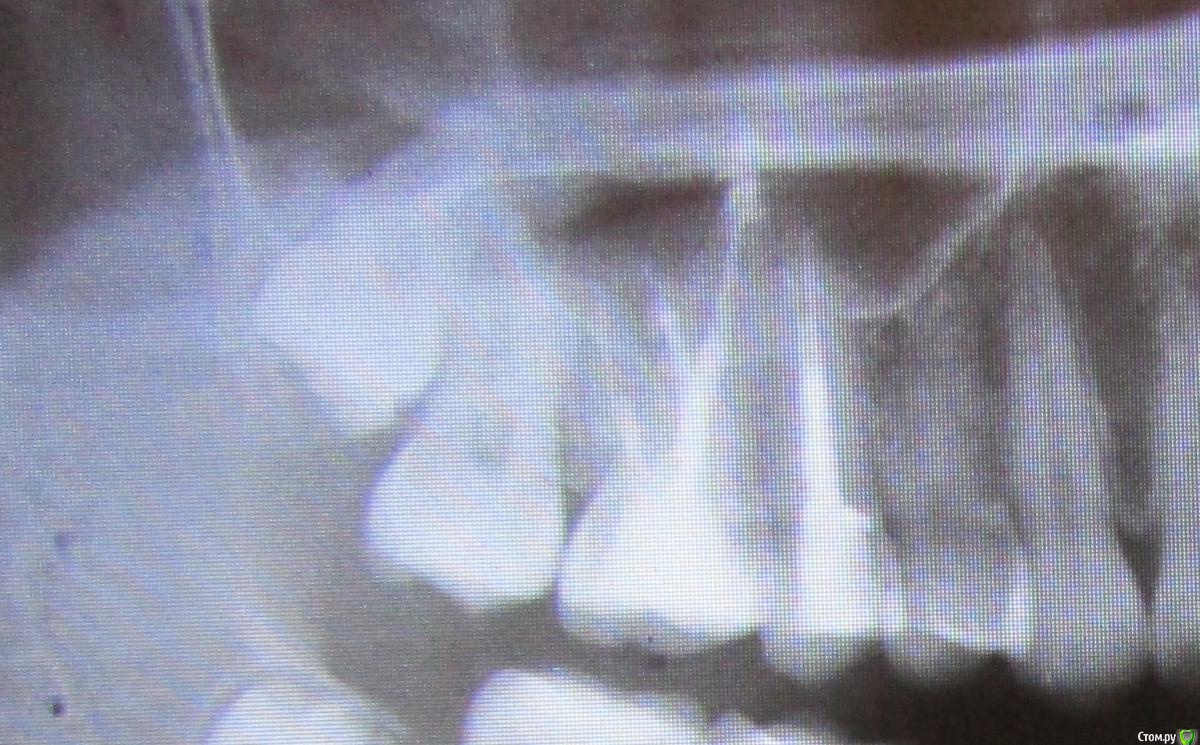

pustoe Опубликовано 13 марта, 2016 Автор Поделиться Опубликовано 13 марта, 2016 Уважаемые врачи, помогите советом! После тройного перелечивания 25 зуба я пол года не обращала внимания на то что чувствую боль при надкусывании. Но надоедает, знаете ли. Ещё раз попыталась понять точно ли 25 болит и выяснила, что боль в 26 зубе. Только при давлении на 1 определённый участок. И боль возникает только при жевании или когда я самостоятельно зубами пытаюсь найти этот участок. На осмотре зуб никак не реагирует ни на давление, ни на воздух, ни на холодную воду. Ну и главное - он мёртвый. Год назад обратилась в клинику, где проводили депульпирование зуба. На снимках врач не нашёл патологий, при ощупывании десны заметил боль в области 28 зуба. Хороший снимок 28 сделать не получилось, направили к хирургу.Посетила хирурга, сделали 3д-томографию. Хирург сказал, что удалять 28 зуб не нужно и проблема в 26, на снимке видна гранулёма. Ниже приложила 2 снимка от хирурга (декабрь 2014 г.). Обратилась в ту же клинику, где лечила 26 зуб , попросила 1) сменить врача, 2) лечить по гарантии. Зуб пролечили (февраль 2015 г.), результаты лечения на снимке №299 (сделан в ноябре 2015 г). Боли при надкусывании появились спустя недели 2-3. Далее в связи с переездом в другой город, не было возможности вновь обратиться к лечащему врачу, поэтому обратилась в новую клинику с целью удалить зуб или наткнуться на профессионалов, которые вылечат меня. В ней посчастливилось услышать аж два мнения разных врачей: терапевт сказал, что все дураки и плохо меня пролечили, надо заново перепломбировать каналы и закладывать лекарства, плюс на 25 зубе обнаружил гранулёму (осмотра физически не произвёл в связи с тем, что на час задержал мой приём и за мной был другой пациент, поэтому времени на меня у врача не было). Второй врач-пародонтолог предложил сделать резекцию. Я согласилась на второй вариант, при посещении пародонтолога описала историю зуба, врач засомневалась в наличии гранулёмы, хотя сказала, что на снимке гранулёма видна. Но раз пришла, решили резать. Разрезали десну, ткани здоровые, куча камня. Провели кютераж, гранулёму не нашли. Насколько я поняла, глубоко рыться в корнях врач не стала в связи с тем, что вариант с гранулёмой отмела. Прошёл месяц, две недели назад начала жевать на этой стороне, боли вернулись. Я в растерянности, вы, врачи с форумов, всегда советуете обратиться очно к специалистам, но я в той ситуации, когда это не помогает. Можно сходить и удалить зуб, но не хочется терять его, да и когда я шла к врачам с этой целью, меня убедили сохранить зуб.Скажите, что мне делать? Что вы видите на снимках ноября (самый актуальный снимок). Как может врач видеть на снимке гранулёму, а при разрезе десны не обнаружить её (в квалификации этого врача сомнений нет)? Как мне избавиться от боли? Может кто-то из вас работает в Санкт-Петербурге и готов взяться за меня?Хочу от вас конкретные советы и комментарий к снимку. Ссылка на комментарий

pustoe Опубликовано 13 марта, 2016 Автор Поделиться Опубликовано 13 марта, 2016 Ниже актуальный снимок в лучшем качестве Ссылка на комментарий